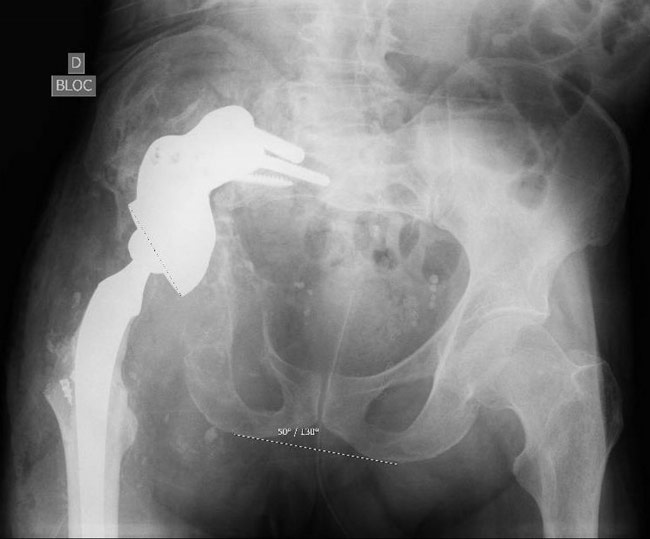

A removal of the cup (in the sciatic nerve) was done.

A Removal of the cup (in the sciatic nerve) was done

2 months after (without weight bearing and denutrition) a complex cup revision was performed.

A complex cup revision was performed